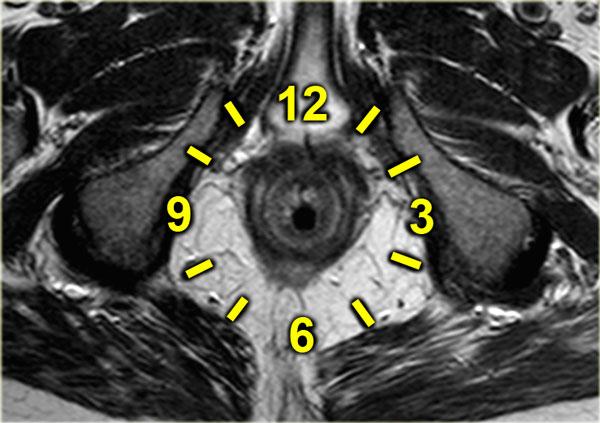

- Vị trí lỗ mở niêm mạc trên hình ảnh axial (sử dụng mặt đồng hồ hậu môn).

Hình vẽ bên trái minh họa mặt đồng hồ hậu môn, tương ứng với góc nhìn của phẫu thuật viên vào vùng quanh hậu môn khi bệnh nhân ở tư thế nằm ngửa có đặt chân lên giá đỡ (2).

Sơ đồ này tương ứng với hướng của các hình ảnh MR axial vùng quanh hậu môn.